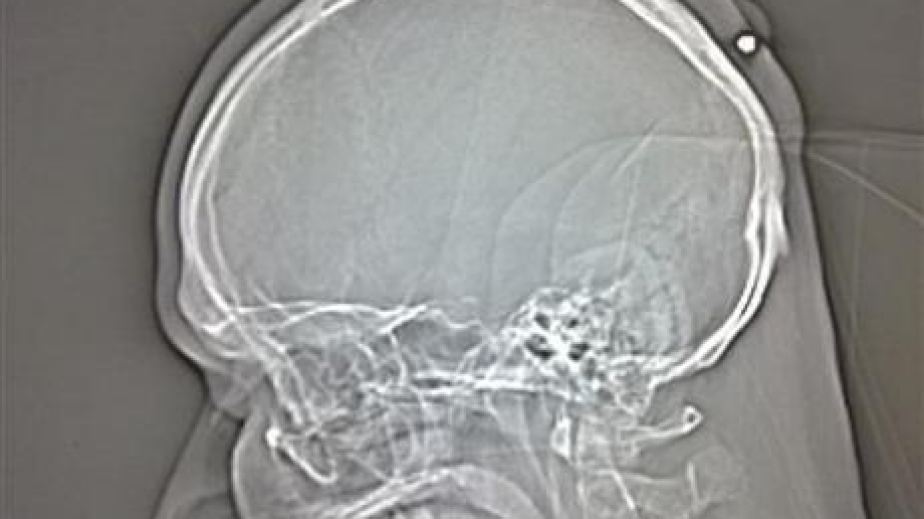

Поляк, който живее в Германия, разбра, че е прострелян в главата 5 години след инцидента, съобщава Ройтерс. Инцидентът станал докато бил пиян, посрещайки новата 2005 година.35-годишният мъж мислел, че има киста и отишъл на лекар. Медиците обаче установили, че в задната част на главата му има куршум 22-ри калибър. Проектилът бил с големина 3,6 мм.На празненството полякът усетил, че нещо го ударило по главата, но след това забравил, защото бил много пиян."Каза ни, че си спомня, че имал ужасно главоболие, но не чак толкова, че да отиде на лекар", твърдят медиците.Раната заздравяла около куршума.35-годишният поляк обаче забелязал, че има бучка и затова потърсил лекарска помощ.Според полицията проектила се е забил в черепа на мъжа, след рикошет от изстрел по случай тържеството.Куршумът ще бъде изваден от главата на поляка в петък.